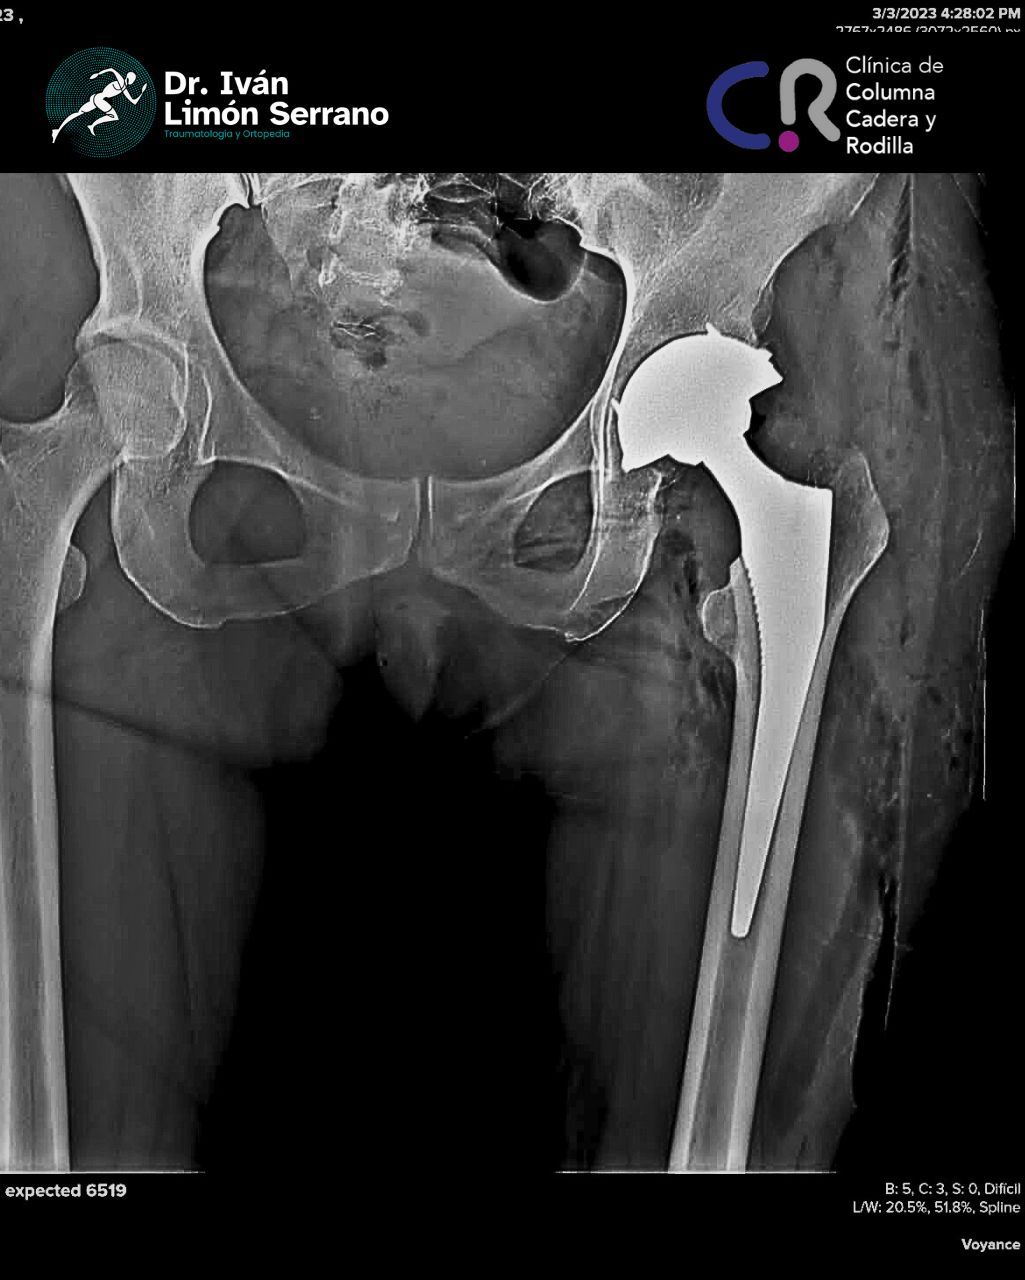

• Prótesis de cadera

• Cirugía cadera